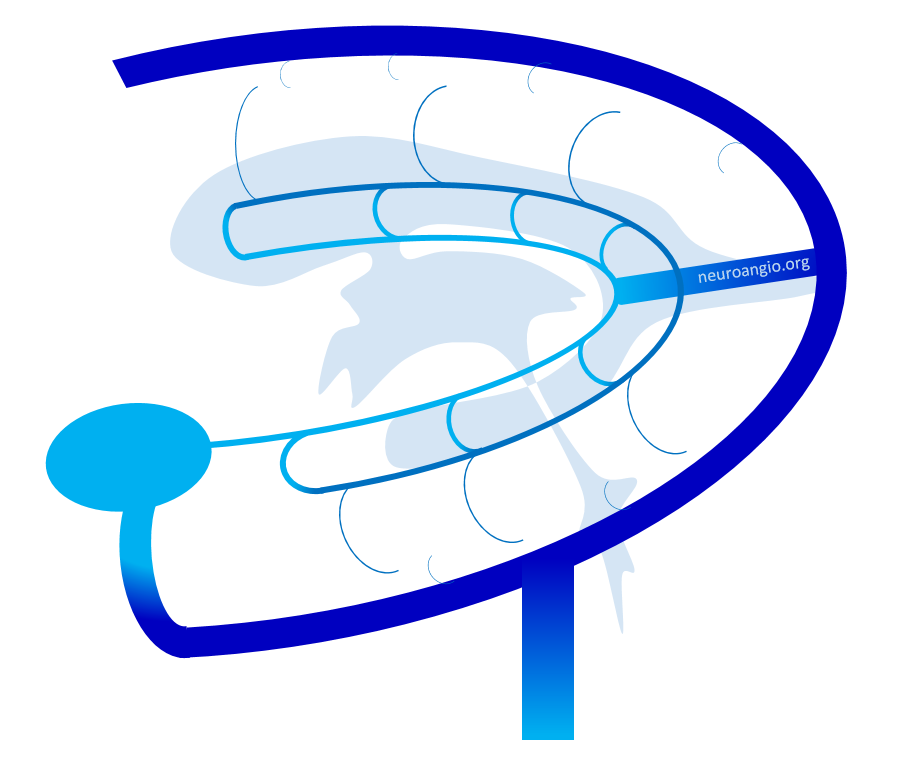

Here is a diagrammatic way of showing the same thing